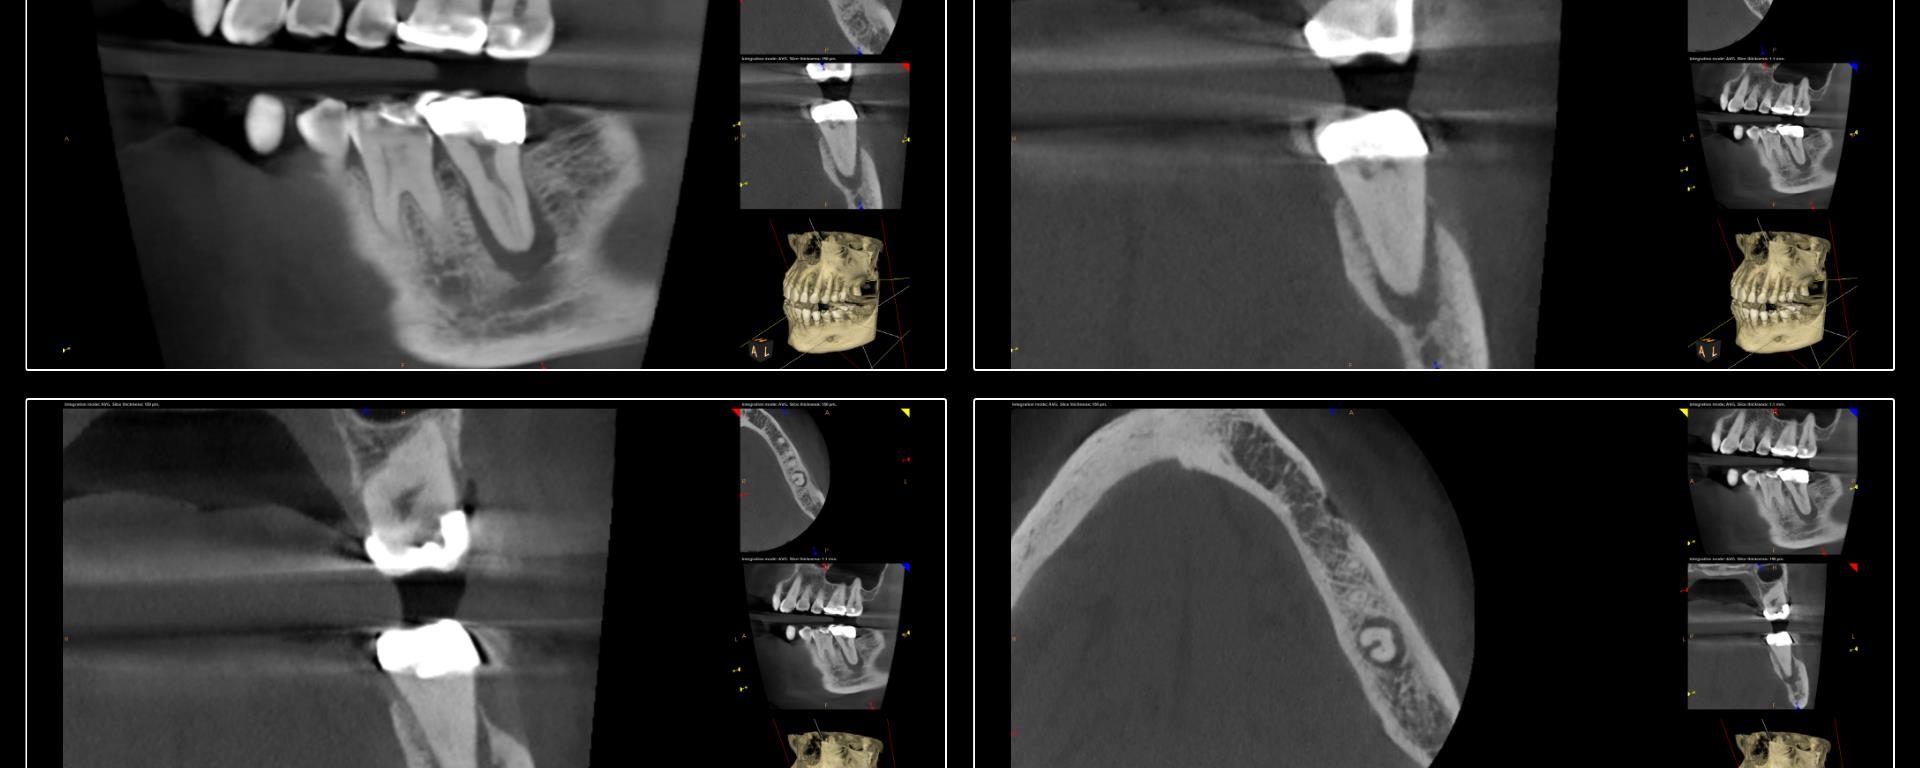

This was a finish from last week.  The largest file used was a 20.  The innovation of the heat treated files allow us to be more conservative from the access to the instrumentation. -Charles